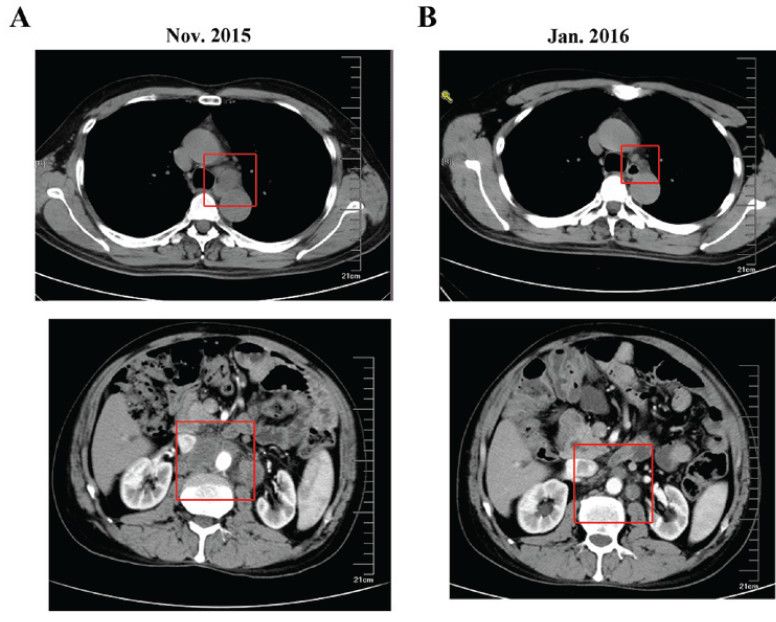

2015年11月,复查CT:纵隔、腹膜后淋巴结转移(图3)。

2016.01,复查CT示纵隔、腹膜后淋巴结缩小(图3),肿瘤标志物降低(图5)。

图3. 纵隔及腹膜后结节变化